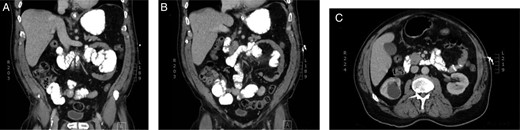

A 69-year-old Caucasian male was admitted to the hospital due to abdominal pain of ∼20 h duration. He described the abdominal pain as ‘achy’, constant, diffuse and with no radiation. Associated nausea and similar episodes of pain over the past 2 years were noted. Patient denied vomiting, fever, weight loss or change in bowel habits or urination. Only significant past medical and surgical history being prostate cancer treated with radiation. On examination, the patient appeared in mild distress and vital signs within normal limits. Physical exam revealed a moderately distended abdomen with an initially incarcerated umbilical hernia. The hernia was able to be manually reduced, which resulted in slight decrease of pain. Hematological and biochemical studies were within normal limits, and a computed tomography (CT) scan demonstrated borderline dilated loops of proximal small bowel; however, no transition point was identified. After discussion with a radiologist, a partial small bowel obstruction secondary to possible LPDH was confirmed (Fig. 1).